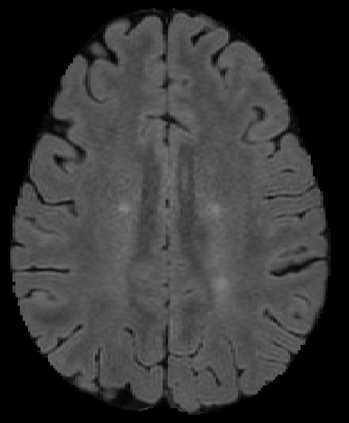

The detection of new multiple sclerosis (MS) lesions is an important marker of the evolution of the disease. The applicability of learning-based methods could automate this task efficiently. However, the lack of annotated longitudinal data with new-appearing lesions is a limiting factor for the training of robust and generalizing models. In this work, we describe a deep-learning-based pipeline addressing the challenging task of detecting and segmenting new MS lesions. First, we propose to use transfer-learning from a model trained on a segmentation task using single time-points. Therefore, we exploit knowledge from an easier task and for which more annotated datasets are available. Second, we propose a data synthesis strategy to generate realistic longitudinal time-points with new lesions using single time-point scans. In this way, we pretrain our detection model on large synthetic annotated datasets. Finally, we use a data-augmentation technique designed to simulate data diversity in MRI. By doing that, we increase the size of the available small annotated longitudinal datasets. Our ablation study showed that each contribution lead to an enhancement of the segmentation accuracy. Using the proposed pipeline, we obtained the best score for the segmentation and the detection of new MS lesions in the MSSEG2 MICCAI challenge.